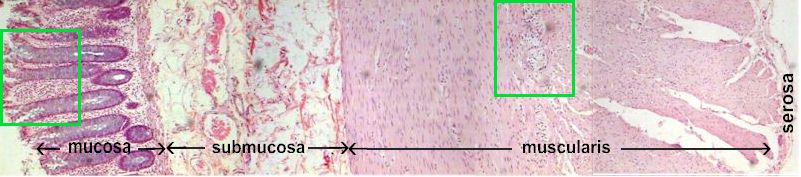

Large Intestine Microscopic Cross Section

Mucosal layer on the surface is made up simple columnar cells and a mucosal muscularis on the deep side .

Submucosa contains fibrous connective tissue and blood vessels.

The muscularis externa is made up of a circular and a longitudinal muscle layer with a myenteric plexus in between the layers.

A very thin layer of Serosa is also present .

Click on the green squares to see details of the muscosa and muscularis externa.